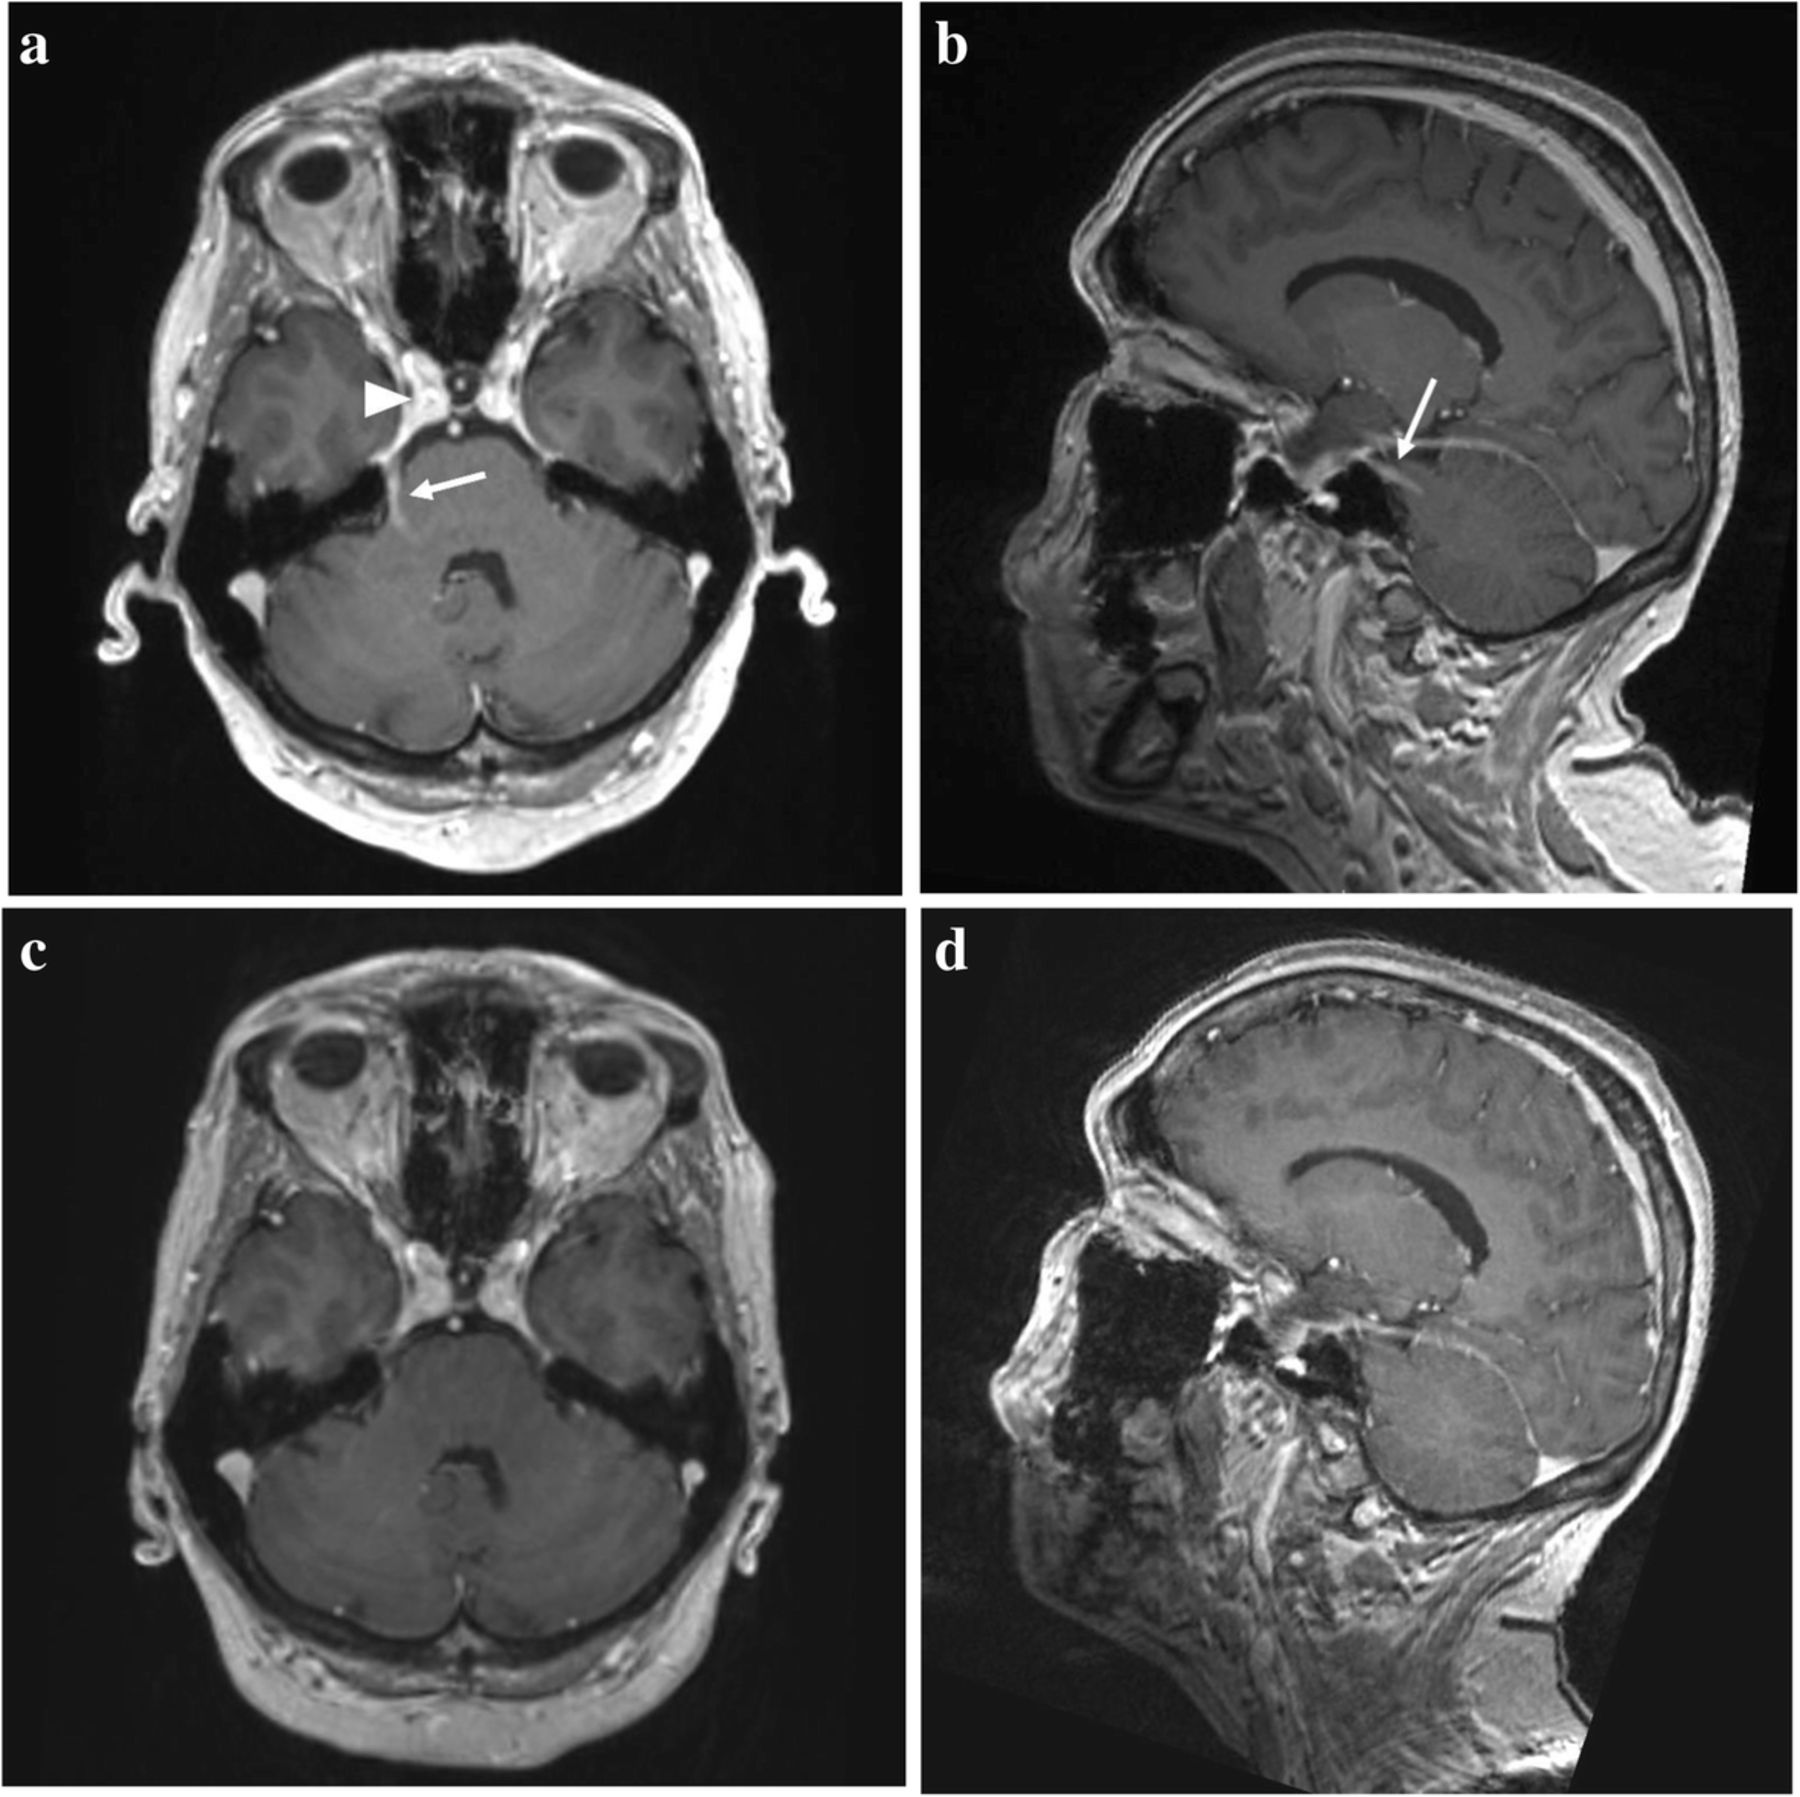

Imaging Characteristics Of Children With Auditory Neuropathy

A Nine Years After Translabyrinthine Resection 5 Years After